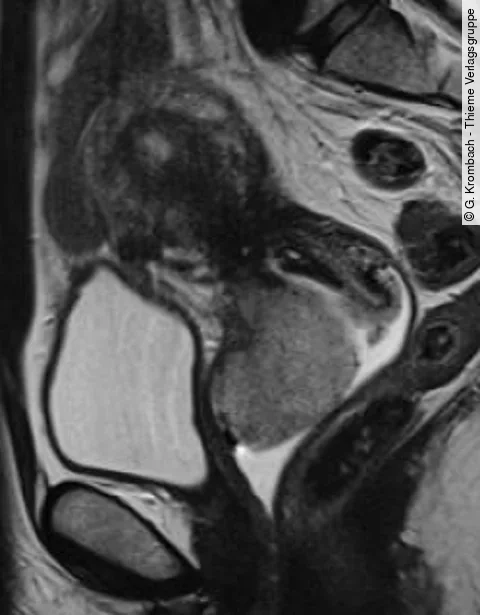

Hoffnung im Kampf gegen Tumore: Bösartige Leberzell- und inoperable Bauchspeicheldrüsentumore sowie gutartige Gebärmuttertumore können vielversprechend mit dem hoch-intensiven fokussierten Ultraschall (USg-HIFU) behandelt werden.